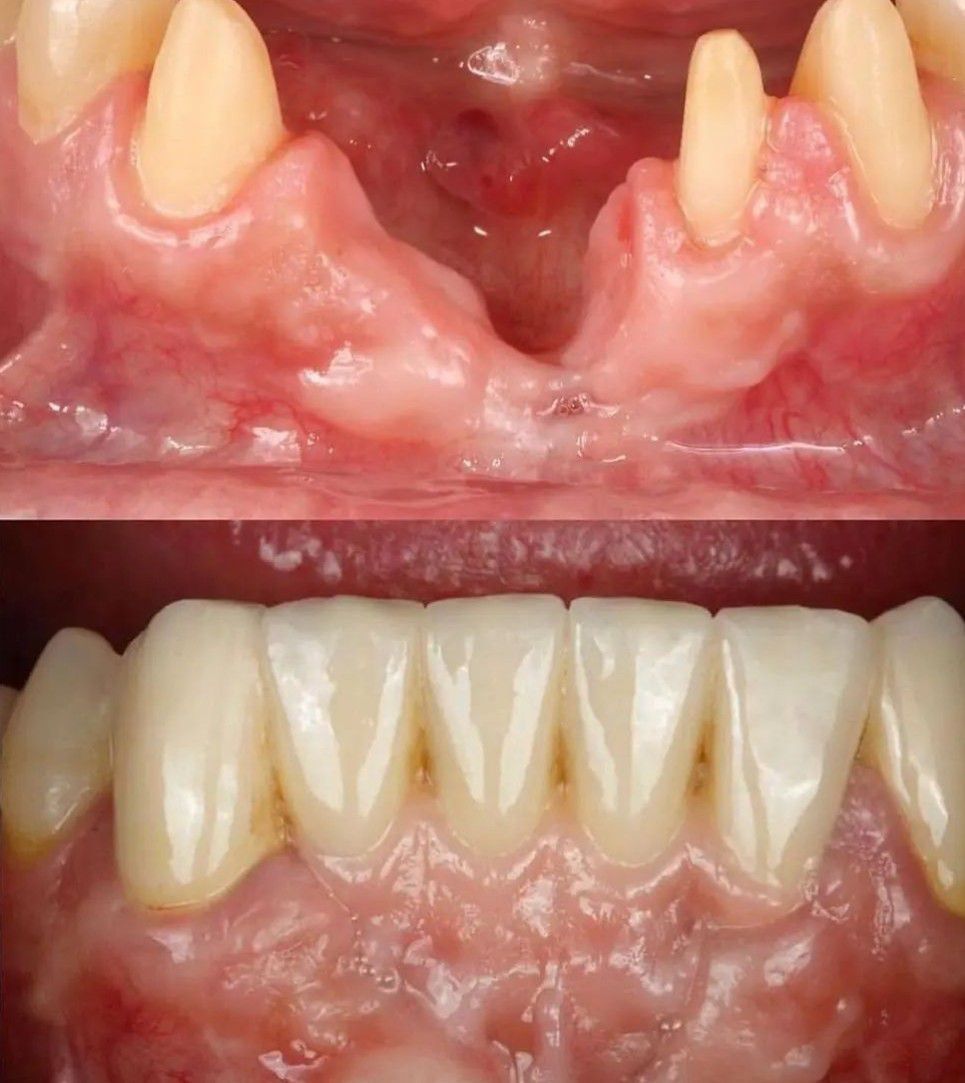

Definitive Prosthesis

A 56-year-old patient wants a definitive prosthesis... without surgery. In this case, we extract the implant and make a metal-ceramic bridge with pink ceramic.